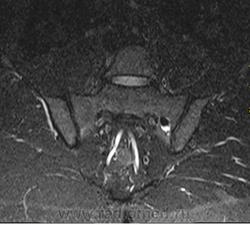

Случай 2: Внутрикостная пневмоцистика

Внутрикостная пневмоцистика